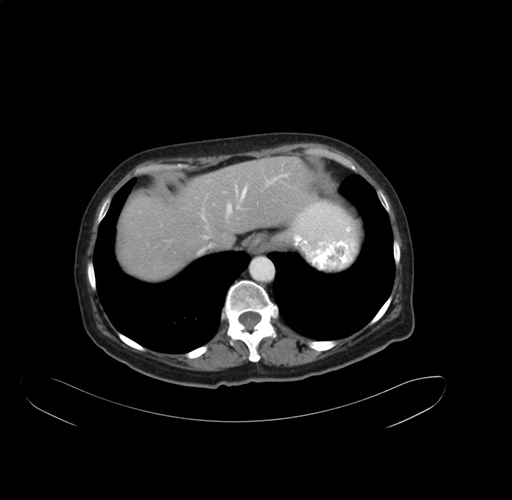

Axial Venous